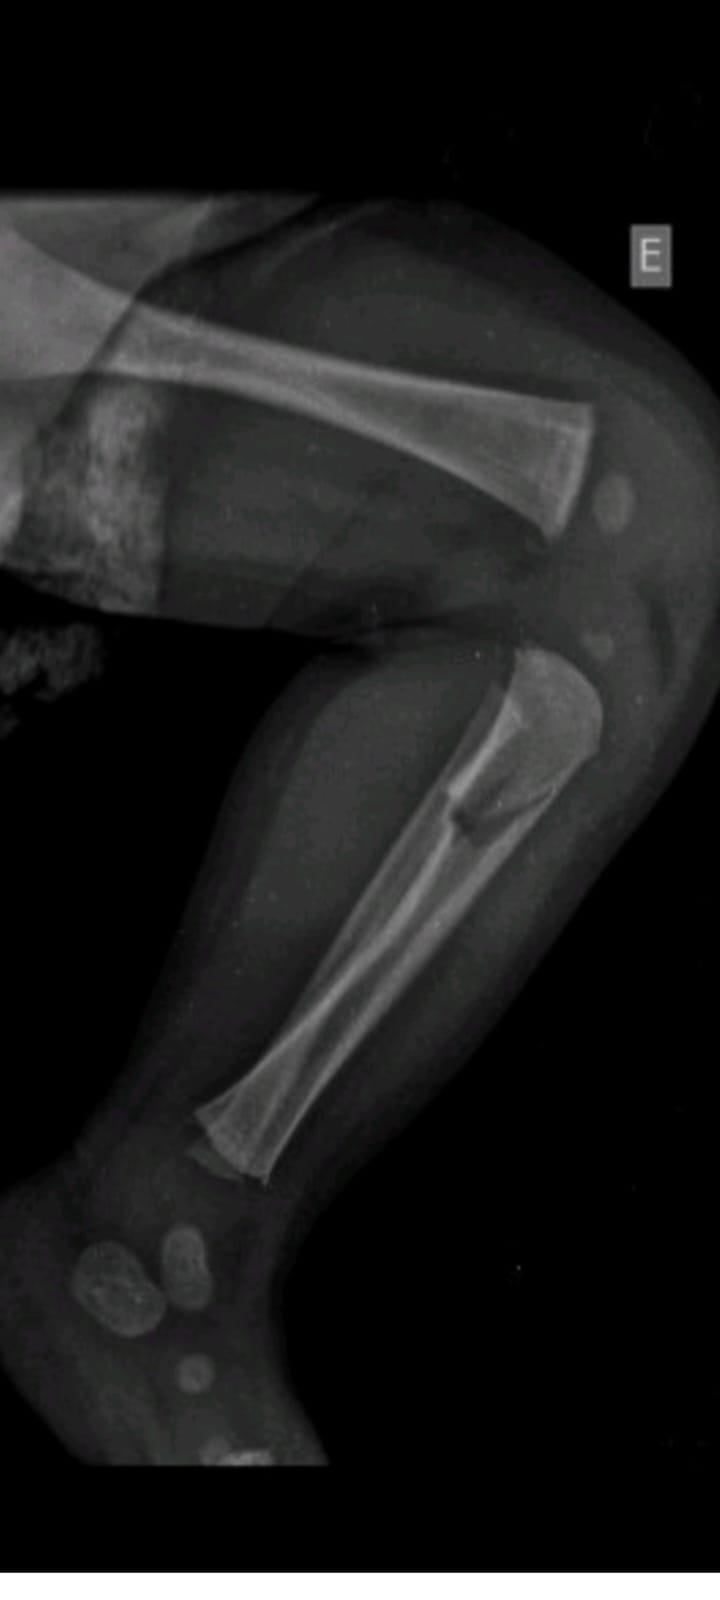

A criança, um menino, apresentava além de vários hematomas e escoriações pelo corpo, em exames aprofundados se constatou lesões ósseas em uma das tíbias, em um antebraço, além de costelas.

Laudo Médico apontou ainda que tais ferimentos expuseram o menino a risco de vida.